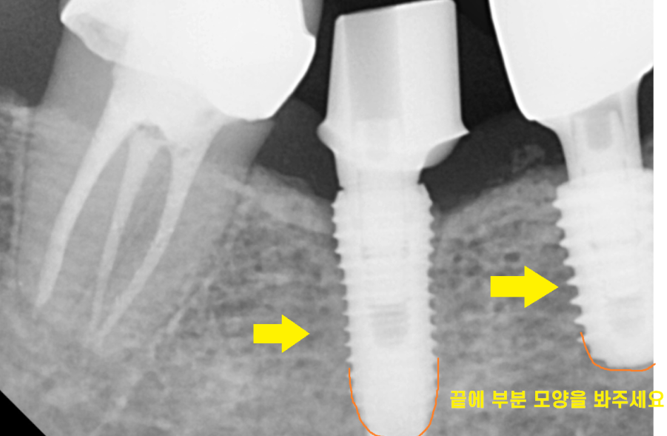

보시면 양쪽 임플란트 모양이 다르게 생겼죠?

다른 회사 제품이라는 뜻입니다.

임플란트 만드는 회사마다 디자인도 규격도 다 다릅니다~!

임플란트 as 할 때 제일 문제점은

어떤 회사 임플란트인지 알아내는 것입니다.

뿌리 끝 다른거 보이시죠?

수백개의 임플란트 회사 제품 사진을 비교하여

제품을 알아내긴 했는데...

해당 환자분도 저희 병원에서 사용하는 임플란트는 아니었습니다.